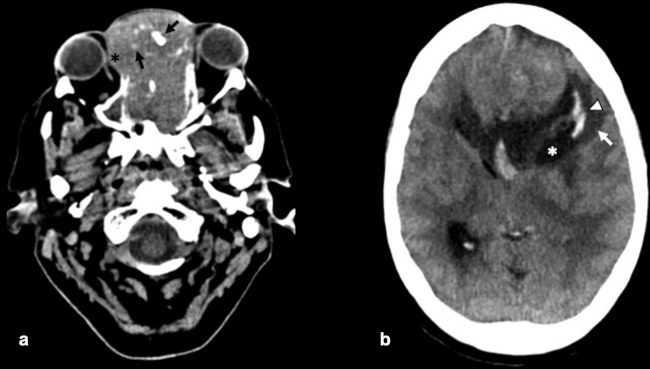

La TC de corte fino (espesor de corte de 1 mm) con reconstrucciones en plano coronal y sagital, es la mejor prueba de imagen inicial para el estudio del NBO. En la TC, aparece como una masa homogénea de tejido blando en la bóveda nasal con realce moderado y uniforme (►Figs.1y2). Se pueden encontrar calcificaciones punteadas dispersas (►Figs.2,3,4,5a,6).50 El valor principal de la TC es una mejor definición de la afectación ósea en comparación con la RM. La TC ayuda a evaluar la erosión ósea de la placa cribiforme, la fóvea etmoidal y la lámina papirácea (►Figs.1,2,3,4,5a,8). Sin embargo, la remodelación ósea sin erosión puede presentarse en algunos casos debido a su patrón de crecimiento indolente.3,35,49 Los estudios de TC generalmente revelan un patrón lítico y muy raramente hiperostosis dominante que simula displasia fibrosa.51 La TC también es útil para evaluar la presencia de metástasis regionales en cuello y a distancia.52,53

La RM es la prueba de imagen de elección para evaluar los detalles de la extensión y la estadificación locorregional del tumor. La RM es superior a la TC para determinar el grado de afectación del tejido blando (►Fig. 9) con una mejor evaluación de la afectación intracraneal (►Figs.10,11,12,13,14), orbital (►Figs.14y15), de la base del cráneo y la invasión perineural.53,54 La RM tiene un valor añadido para distinguir la afectación dural de la del parénquima cerebral (►Fig. 12).55 En la RM, el NBO aparece hipointenso respecto a la sustancia gris en imágenes ponderadas en T1 y de isointenso a hiperintenso en las imágenes ponderadas en T2 (►Figs.10,11,12,13,14,15).56 Muestra un realce homogéneo, excepto en áreas con hemorragia o necrosis. Además, permite diferenciar las secreciones retenidas del tumor, al ser estas hiperintensas ponderadas en T2.53,55 Los hallazgos de imágenes clásicos incluyen una masa “en forma de mancuerna” que se extiende a través de la placa cribiforme (►Fig. 12), con la parte estrecha a nivel de la placa. Los quistes tumorales periféricos (►Figs.5b,12,14,16) y las calcificaciones moteadas son bastante característicos de NBO.1